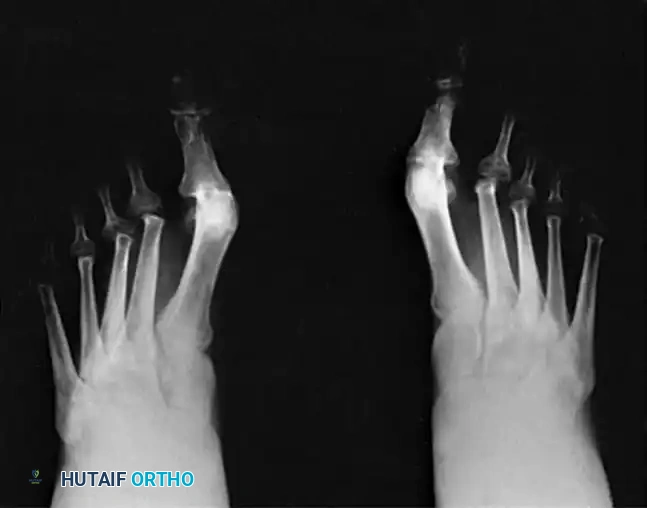

The classic "rheumatoid foot" presents with severe hallux valgus, dorsal subluxation or frank dislocation of the lesser metatarsophalangeal (MTP) joints, claw toes, hammer toes, and the formation of painful adventitial bursae. As the proximal phalanges subluxate dorsally, the plantar metatarsal fat pad is drawn distally, leaving the prominent metatarsal heads directly exposed to plantar pressure, leading to intractable plantar keratoses and ulceration.

Forefoot arthroplasty is directed primarily at the severe metatarsophalangeal joint deformities. The overarching goals are to relieve pain, correct deformity, improve cosmesis, enhance ambulatory function, and allow the patient to wear a reasonable variety of footwear.

Regardless of the specific surgical approach (plantar vs. dorsal incisions), adequate bony resection is mandatory. The phalanges must be allowed to realign loosely with the metatarsal remnants without any soft tissue tension. Insufficient relaxation of the soft tissues around the MTP joints due to inadequate bone resection will severely compromise the result, leading to recurrent dorsal subluxation and stiffness.

The Metatarsal Cascade

When performing a resection arthroplasty, the surgeon must carefully contour the remaining metatarsal necks. Unequal lengths of the metatarsal remnants, or metatarsals that do not cascade in a gentle, parabolic curve from metatarsals two through five, will result in transfer metatarsalgia and a compromised outcome. Furthermore, any bony fragments left in the forefoot weight-bearing pad will act as symptomatic pebbles, causing severe localized pain.

Surgical Options for the Lesser Rays

Resection of all five metatarsal heads, or fusion of the first MTP joint combined with resection of metatarsals 2 through 5, have both been shown to produce excellent results. All four of the lesser toes must be treated in the same manner, regardless of the varying severity of involvement of each individual ray. While there are rare exceptions where only one or two lesser metatarsal heads are removed, the patient must be warned that subsequent surgeries to remove the remaining heads are highly likely as the disease progresses.

ARTHRODESIS OF THE FIRST METATARSOPHALANGEAL JOINT

For the rheumatoid hallux, arthrodesis of the first MTP joint, combined with varying degrees of bony shortening/resection at the lesser MTP joints, is the gold standard. This approach yields satisfactory results in 80% to 90% of patients.